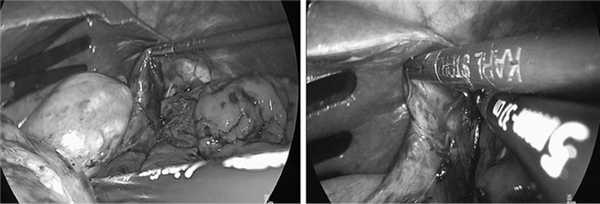

С учетом клинической симптоматики и полученных при обследовании данных решено выполнить иссечение дивертикула желудка лапароскопическим доступом. Под общим обезболиванием после наложения пневмоперитонеума и установки в брюшную полость троакаров при помощи аппарата Ligasure произведена мобилизация дна и кардиального отдела желудка по большой кривизне. Пересечены частично желудочно-ободочная связка, желудочно-селезеночная связка, короткие желудочные сосуды. Выполнена медиальная ротация дна желудка. При помощи интраоперационной эндовидеотрансиллюминации желудка определено, что дивертикул расположен по задней поверхности кардиального отдела желудка ближе к малой кривизне, на 3 см ниже пищеводно-желудочного перехода (рис. 4).

Рис. 4. Мобилизация дивертикула задней стенки кардиального отдела желудка (интраоперационные фотографии).

Из-за явлений перидивертикулита с техническими трудностями выполнена мобилизация дивертикула из рыхлых и плотных его сращений с задней стенкой желудка, после чего дивертикул одномоментно прошит и отсечен у основания сшивающим аппаратом EndoGIA (рис. 5).

Рис. 5. Видеолапароскопическая резекция дивертикула (интраоперационные фотографии).